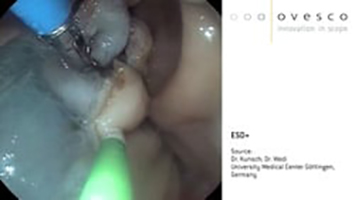

Videos ESD+

Zeigt das ESD+-Verfahren mit dem AWC®